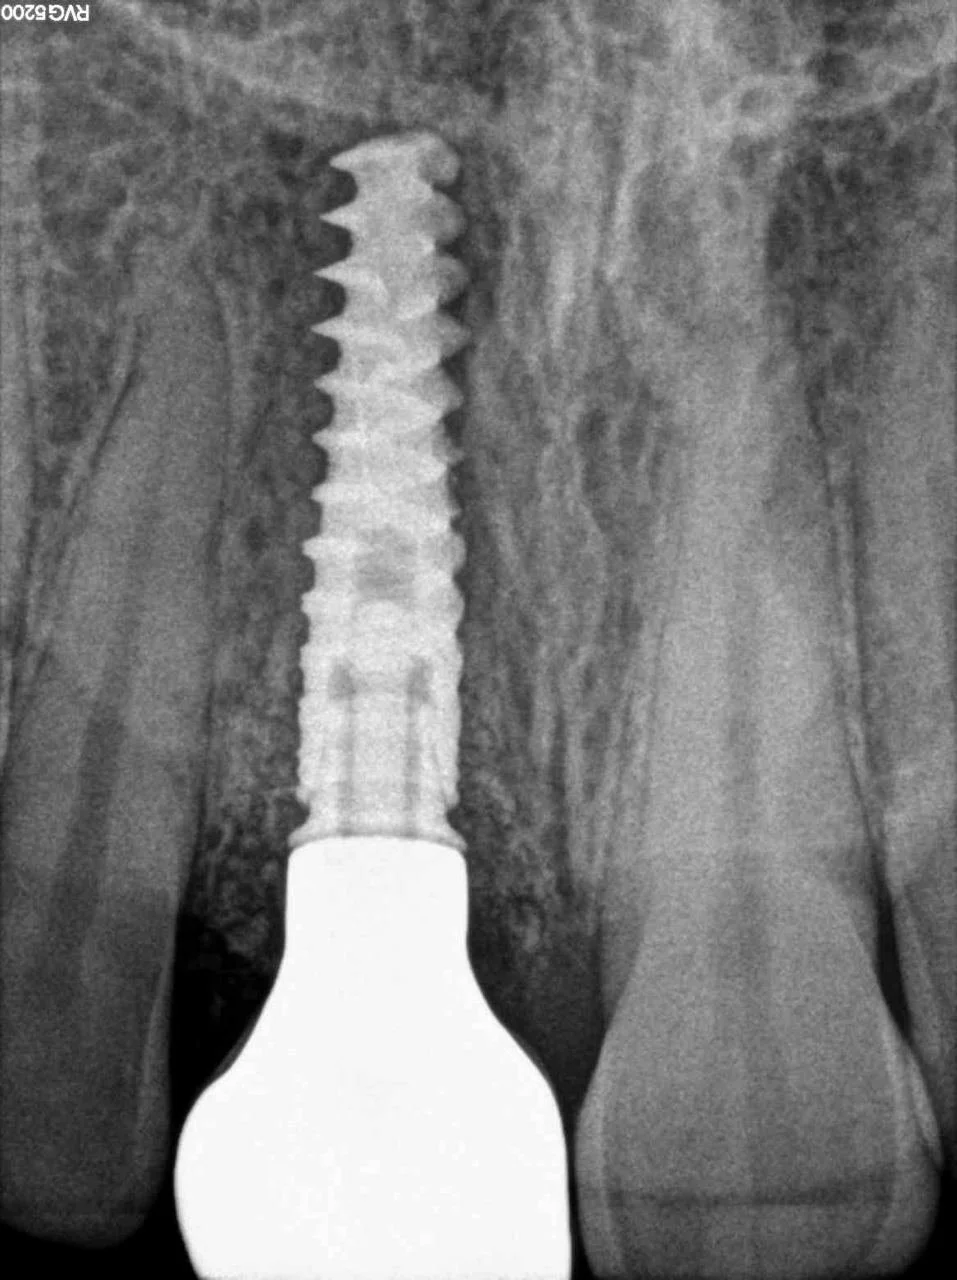

Maxillary Anterior implant supported crown

3. Accurate Implant placement